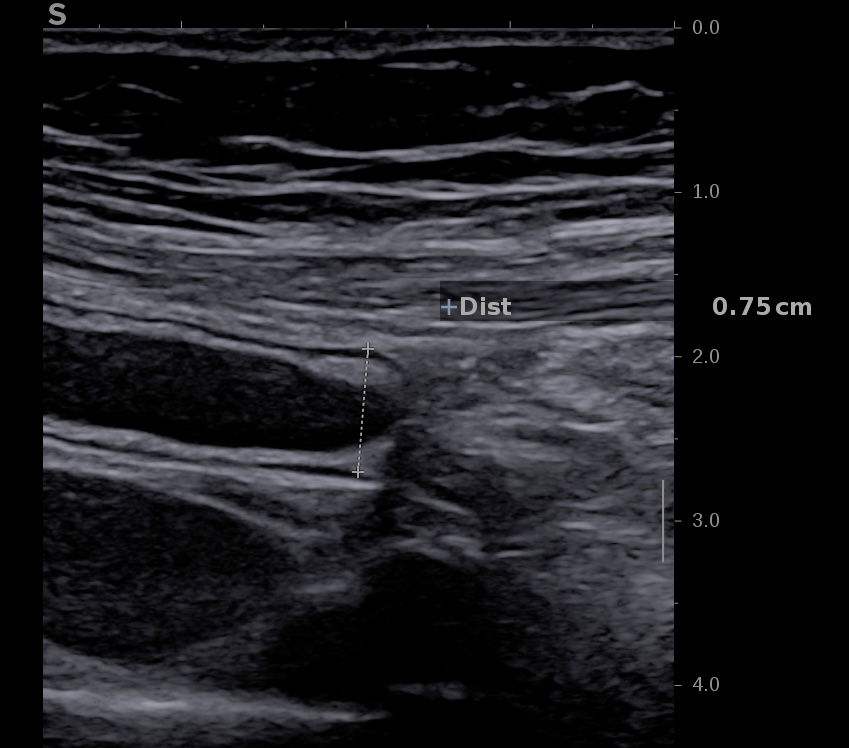

Image échographique de l'appendice au niveau du caecum

Corps de l'appendice vermiculaire distendu (8 mm de large)